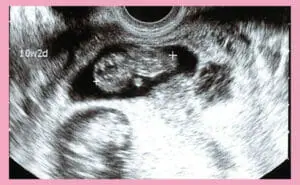

妊娠10週の赤ちゃんの大きさは?症状と注意点まとめ

妊娠11週にできること(エコー写真あり)|ダウン症見つかる?【医…